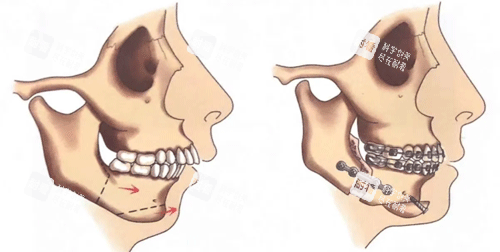

“正颌手术不是切块骨头那么简单,它像在面部搞‘精细拆迁’。”艾伟健医生在诊室里用镊子夹起一块颌骨模型,“上颌要前移3毫米,下颌得旋转5度,咬合关系要像齿轮一样严丝合缝。”他身后的墙上挂着《我国口腔颌面外科杂志》编委的聘书,这是国内颌面领域的头部学术背书。

“很多医生还在用二维CT规划手术,我们已经玩转3D智能化导板8年了。”艾伟健指着墙上挂着的专有证书。这项技术需要把患者的颌面数据输入电脑,通过AI算法模拟出更佳截骨方案,再定制专属导板。

精度革命:传统手术靠医生经验判断截骨量,误差可能达2毫米;3D导板把误差压缩到0.1毫米,相当于在头发丝上刻字